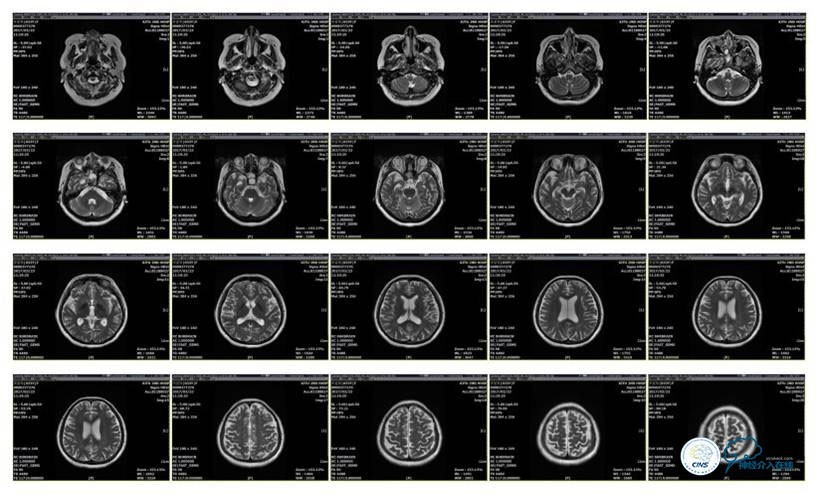

MRI T1

MRI T2

MRV

2016-5-19 MRI

2016-05-20 MRV

2016-06-03 CT

2017-06-07 CT